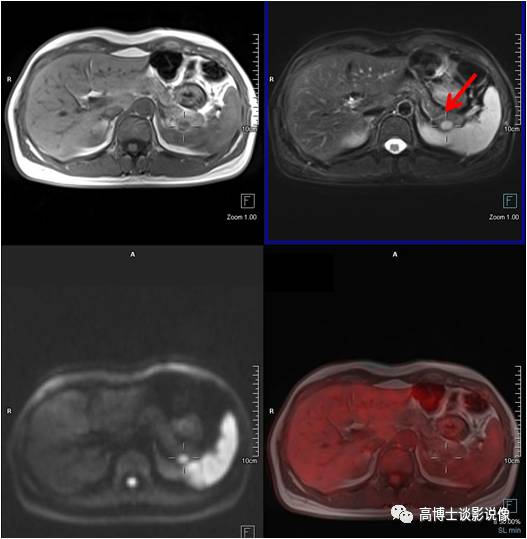

肾上腺腺瘤

中年男性,无任何症状。左侧肾上腺结合部见一长径约1.8cm结节,FDG稍摄取,考虑为肾上腺腺瘤。

点评

根据是否有功能,可分为无功能性和功能性腺瘤。一般来说,偶然发现的肾上腺腺瘤都是无功能性的。对于无功能性腺瘤,注意定期复查。功能性腺瘤需要专科医生进行评估,最好是具备诊断肾上腺肿瘤丰富经验的放射科医师、内分泌医生和外科医生组成的评估小组。

髓样(质)脂肪瘤

中年女性,左侧肾上腺见一大小约1.9cm×2.1cm的类圆形异常信号灶,信号不均匀,内含脂肪信号,考虑为髓样脂肪瘤。

点评:

本病很少出现临床症状,多在体检时偶然发现。如肿瘤较大压迫邻近组织器官或瘤内出血坏死,可引起不适症状。但对于直径较小且无临床症状者应随访观察。